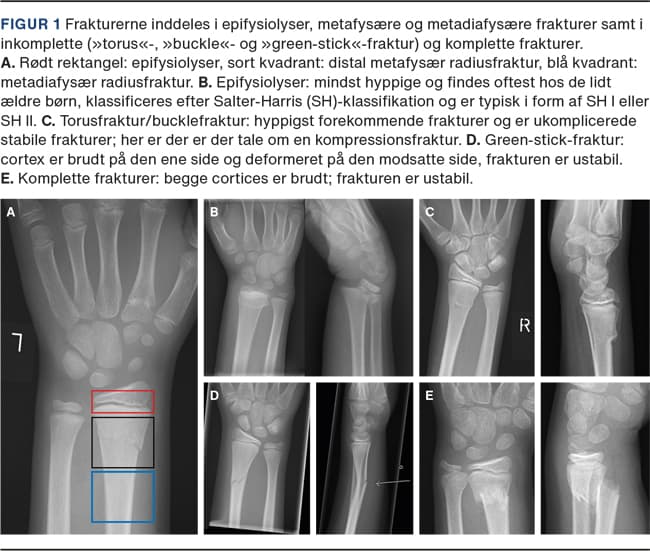

Frakturerne inddeles i epifysiolyser, metafysære og metadiafysære frakturer samt i inkomplette (»torus«-, »buckle«- og »green-stick«-fraktur) og komplette frakturer (Figur 1). Børn har under vækst stor remodelleringsevne, og 75% af længdevæksten og dermed størstedelen af remodelleringen foregår distalt i radius [7]. Evnen til remodellering afhænger af væksthastighed i vækstzonen, restvækst og frakturens afstand fra vækstzonen. Jo tættere frakturen er på vækstzonen, og jo yngre barnet er, des større er remodelleringen. Figur 2 viser et barns evne til at remodellere over tid.